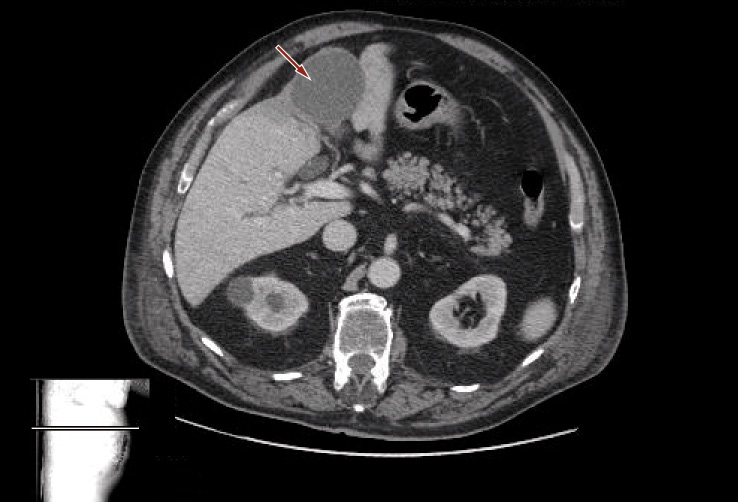

Esclusa la possibilità di una crioglobulinemia secondaria a HCV, a connetivopatie e a malattie autoimmuni (in particolare sindrome di Sjögren e lupus eritematoso sistemico), si procedeva, pertanto, alla ricerca di eventuali foci neoplastici, non rilevati dalla TC addome (Figura 5).

Figura 5. TC addome: fegato nei limiti con multiple areole focali ipodense, avascolari, di natura cistica; formazione espansiva rotondeggiante, del diametro di 6 cm, a densitometria omogenea, fluida, delimitata da sottile pseudocapsula periferica tenuemente vascolarizzata e con presenza di puntiformi calcificazioni parietali in sede superiore; colecisti ipodistesa, completamente occupata da formazioni litiasiche con diametro massimo di 17 mm; milza e pancreas nei limiti; mielolipoma a carico del surrene destro; reni di ridotte dimensioni con spessore corticale marcatamente ridotto e con alcune formazioni cistiche corticali; all’ilo epatico alcuni linfonodi, di cui il maggiore con diametro di 2 cm; al retroperitoneo lombo-aortico e in sede lombo-iliaca alcuni linfonodi con diametro massimo di 12 mm; prostata molto ingrandita e disomogenea; in sede iliaco-inguinale sinistra alcuni linfonodi vascolarizzati del diametro massimo di 11 mm